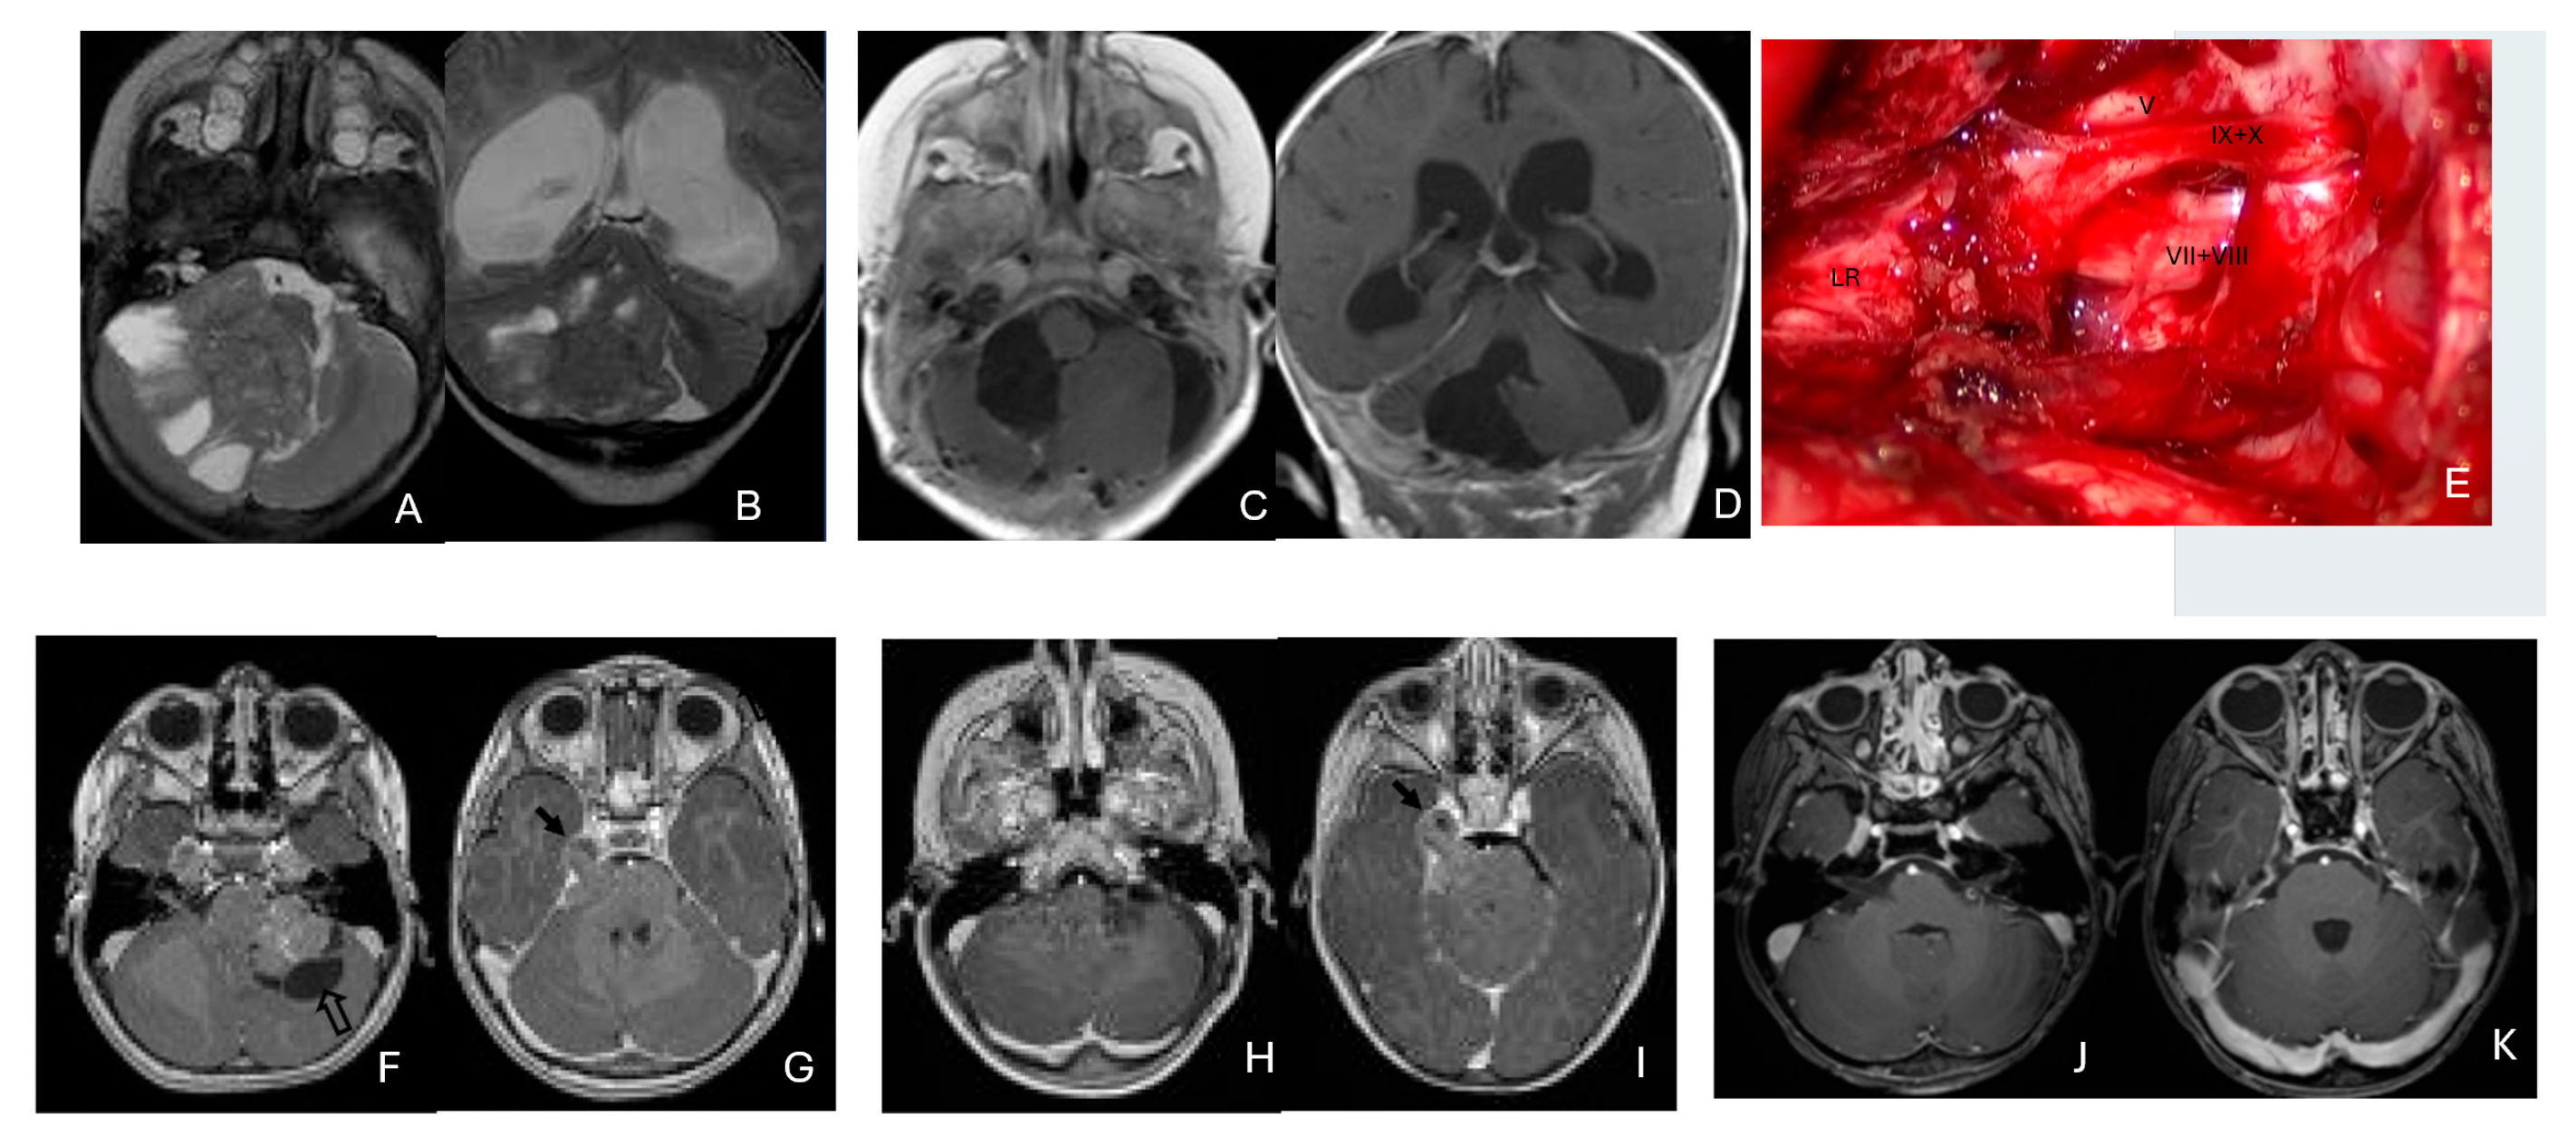

Eleven patients were diagnosed with ATRT in the pineal region, defined in the transverse plane from the posterior third ventricle to the quadrigeminal cistern, and in the vertical plane between the corpus callosum and the superior vermis. Of these, only one patient had a lesion centered in the posterior third ventricle that appeared to arise from the pineal gland (Figure 10A–D).

Figure 10.

Pineal region ATRT. (A–D): MR ((A), axial; (B), sagittal; (C), coronal) of a 3-year-old girl show an avidly enhancing ATRT in the posterior third ventricle. Postoperative post-contrast MR ((D), sagittal) demonstrates gross-total resection. (E–I): MR images ((E), axial; (F), sagittal) of a 13-month-old boy reveals a pineal region tumor extending from the quadrigeminal cistern into the fourth ventricle with obstructive hydrocephalus. The superior vermis and fastigium (open arrow) are depressed, and the tectal plate (solid arrow) is flattened and displaced rostrally. Gross-total resection of largely necrotic ATRT was achieved via a posterior interhemispheric transtentorial approach. Postoperative MR ((G), axial; (H), sagittal) shows restoration of the tectal plate (solid arrow) and fastigium (arrowhead). The superior vermis and the ependymal lining of the fourth ventricle were not invaded. A representative brain section (I) at post mortem study from another patient with a similar presentation demonstrates intact bilateral cerebellar peduncles (arrows) and a preserved tectal plate (arrowhead). Thus, the tumor is considered to arise from the superior medullary velum.

The remaining ten tumors of the pineal region, which constitute the majority, were found to originate from the superior medullary velum (SMV) [20,21]. Characteristic neuroimaging features included posterior displacement of the superior vermis and fastigium, as well as rostral displacement of the tectum, accompanied by a mass occupying the quadrigeminal cistern and the upper fourth ventricle (Figure 10E,F). Postoperative MRI following the resection of tumors arising from the SMV demonstrated preservation of both the cerebellar vermis and the tectum (Figure 10G,H). A postmortem examination of an ATRT involving the SMV revealed a defect in the roof of the fourth ventricle, with intact superior cerebellar peduncles and tectal plate—findings that strongly suggest an origin from the SMV (Figure 10I). Among the ten patients with SMV ATRT, eight exhibited central necrosis or varying degrees of cyst formation, while one patient presented with evidence of intra-tumoral hemorrhage. All patients with ATRT in the pineal region experienced hydrocephalus, and only one patient showed MRI evidence of subarachnoid dissemination at the time of diagnosis.

The mean age at diagnosis for patients with pineal region AT/RT was 12.4 months, with most cases occurring in infancy (approximately 9 months).